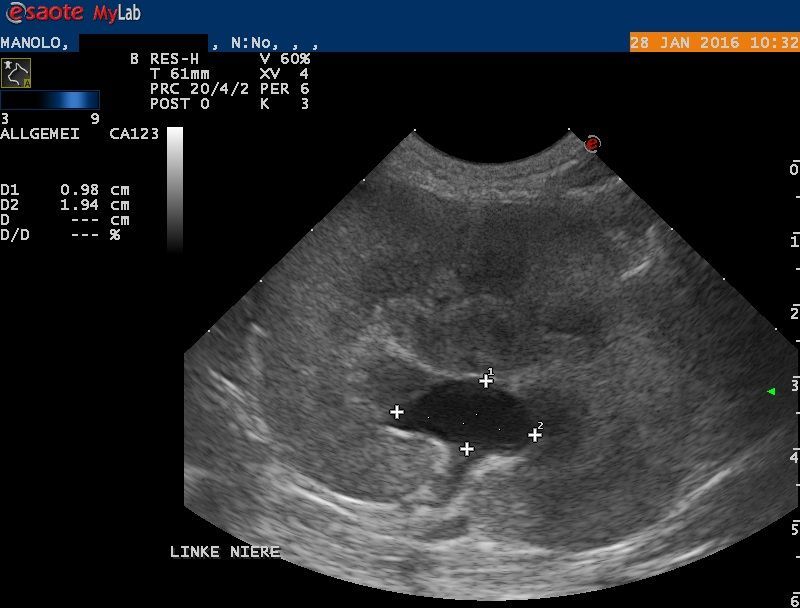

Der Bauch von Manolo wird mittels Ultraschall untersucht: Die rechte Niere erscheint klein und weist eine veränderte Architektur auf. Die linke Niere ist deutlich vergrössert; das Nierenbecken ist erweitert, und auch der ableitende Harnleiter ist deutlich erweitert. Im Nierenbecken findet sich ein kleiner Nierenstein von ca 4x2x2 mm Grösse. Mittels steriler Punktion wird Urin aus der Harnblase entnommen - im Urin befinden sich grosse Mengen rote und weisse Blutkörperchen sowie Baktieren, auch ist der Harn wenig konzentriert.

Die Erweiterung des Beckens und des Harnleiters (Ureter) der linken Niere weisen auf eine Blockade des Harnleiters hin, welcher den Urin von der Niere in die Blase transportieren sollte. Durch die Blockade wird Urin gestaut und das Nierenbecken und der vor der Blockade liegende Teil des Ureters quasi "aufgeblasen". Die Folge ist eine Funktionsstörung der Niere, wodurch sich die Nierenwerte im Blut erhöhen. Die beobachteten Veränderungen der rechten Niere könnten darauf hinweisen, dass auch dieses Organ in der Vergangenheit eine ähnliche Schädigung erlitten hat - dadurch, dass die linke (damals gesunde) Niere noch normal funktionierte, wurde diese Schädigung möglicherweise nicht bemerkt.